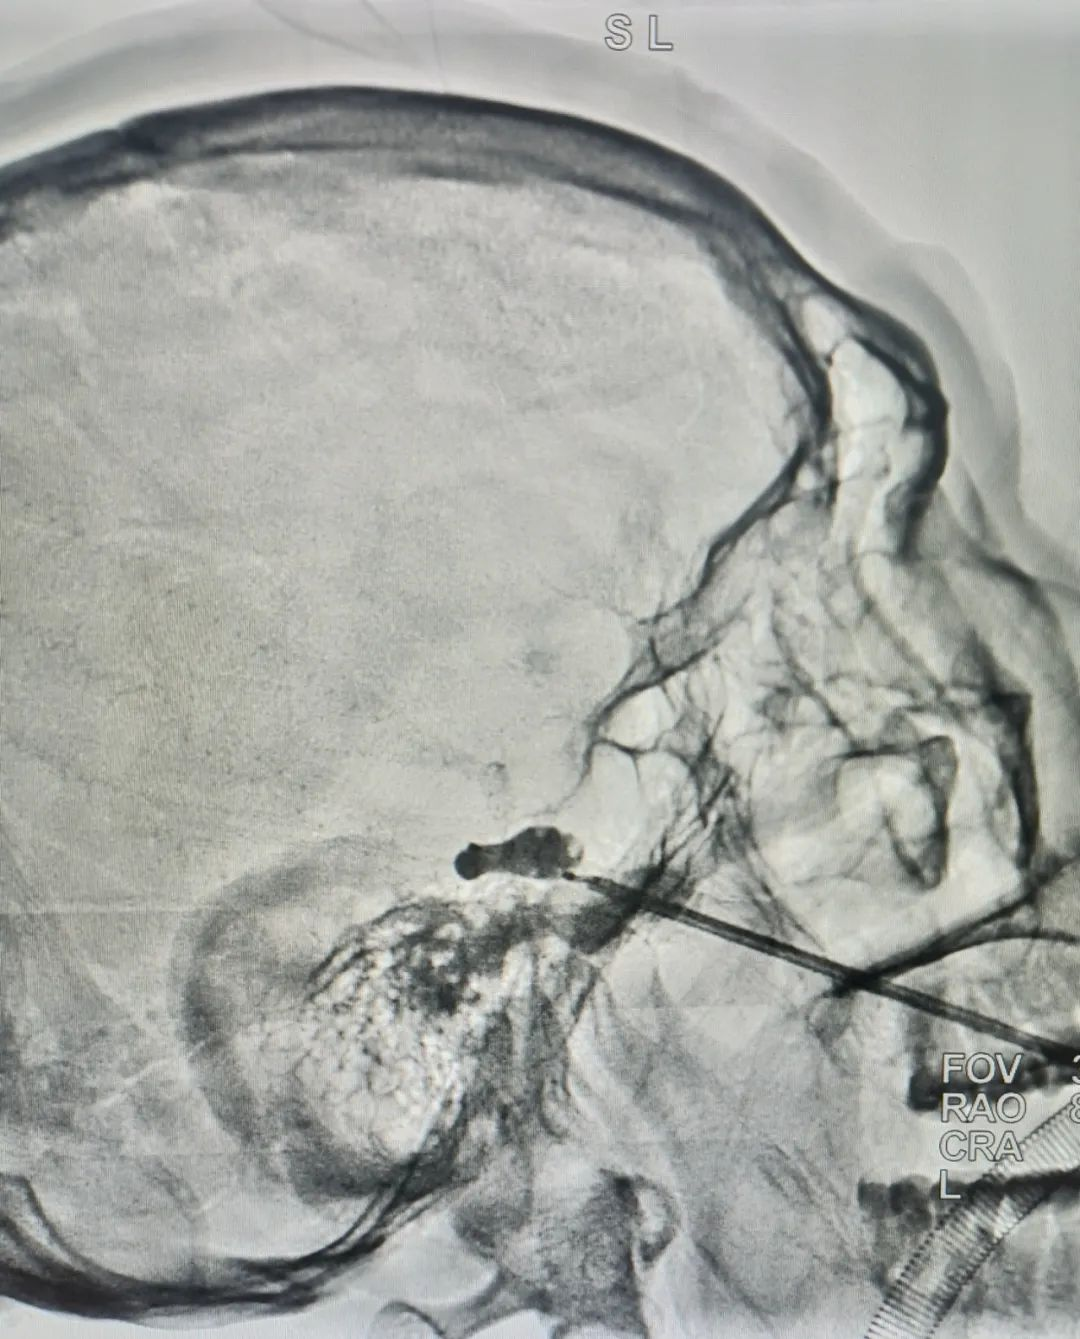

术中影像